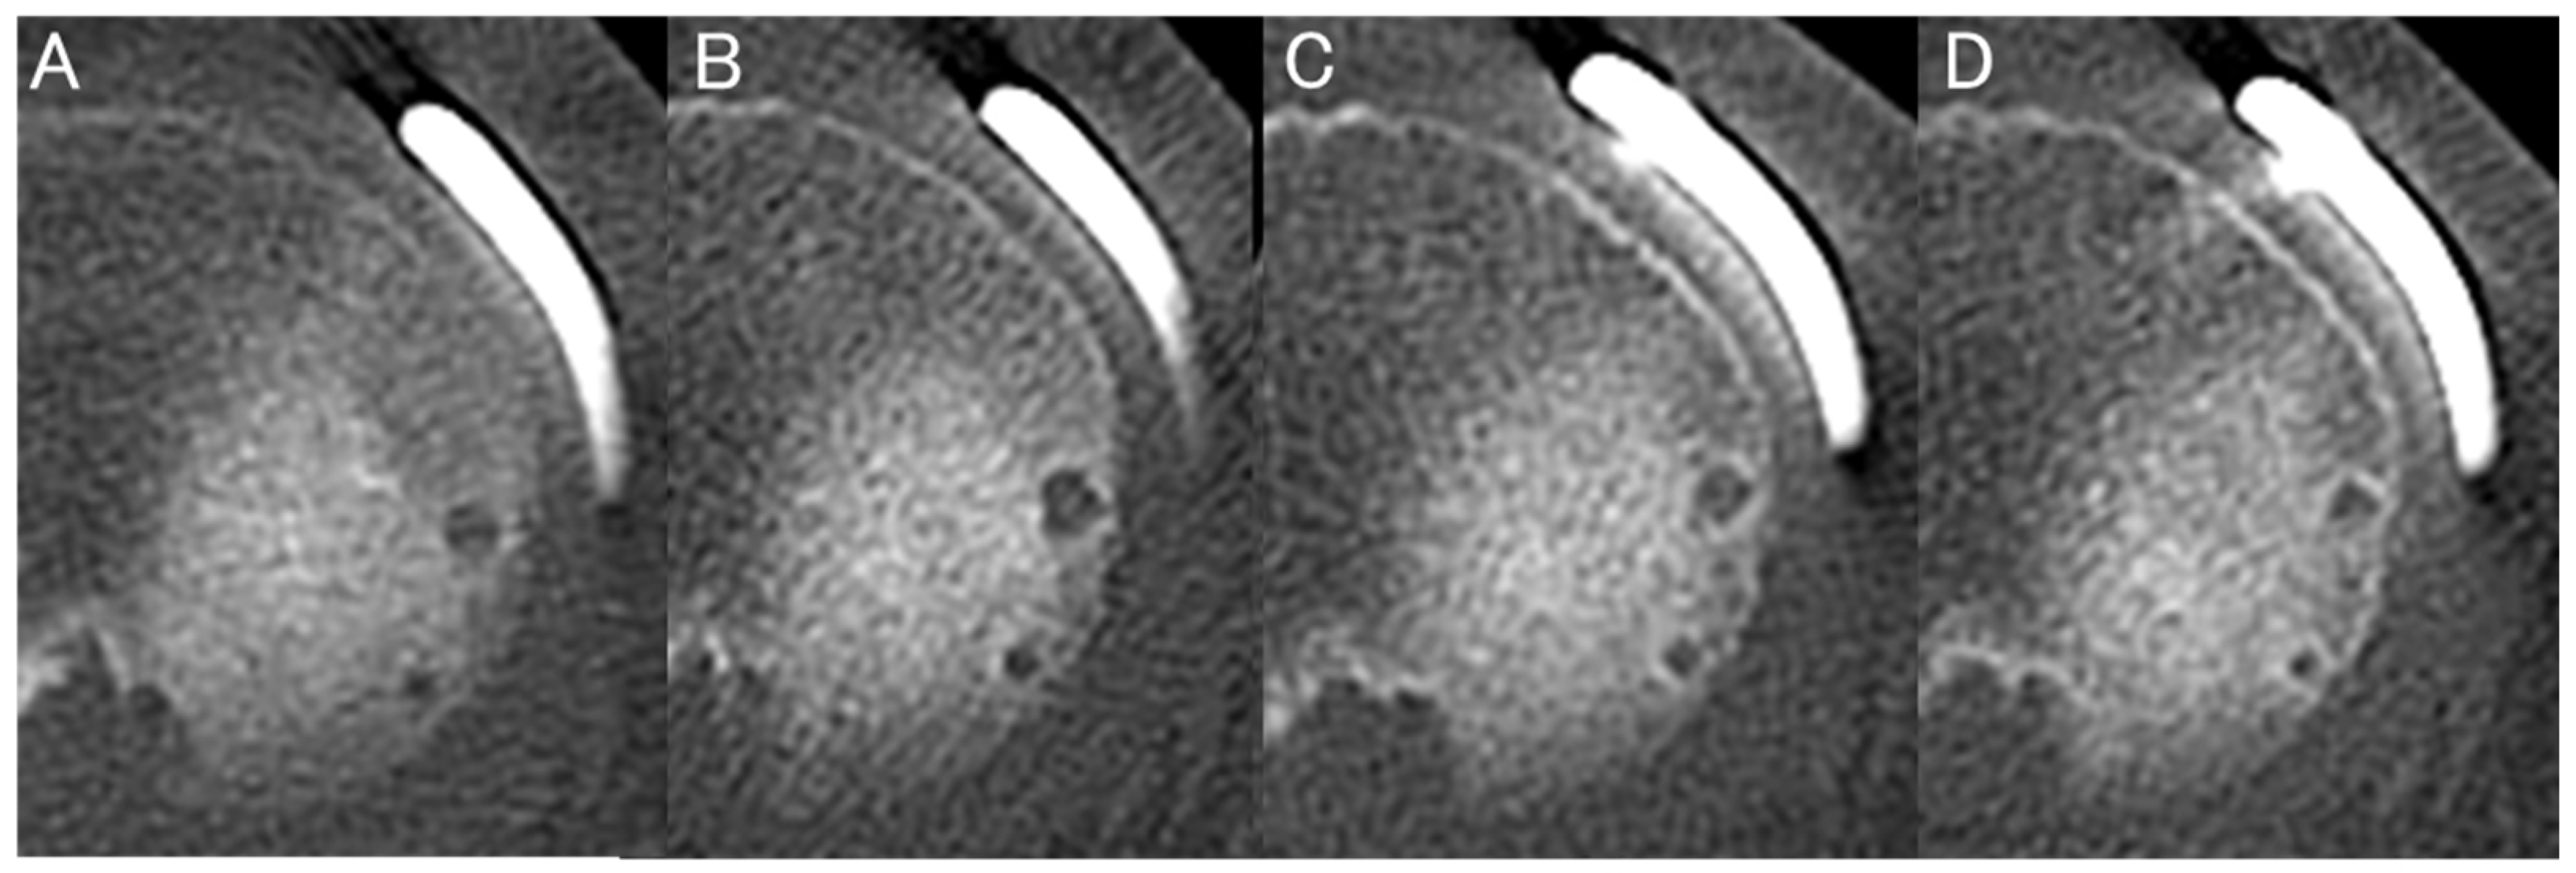

Representative serial MPR CT images obtained at 1, 3, 6, and 1 year postoperatively are shown in Figure 6. AHW increased at 1 month, reached its maximum at approximately 3 months, and subsequently decreased with surrounding sclerosis by 6 months to 1 year. At the R-anchor, both ML-AHW and AP-AHW showed a decreasing trend over time. AP-AHW decreased significantly from 2.4 ± 0.8 mm at 1 month to 1.9 ± 1.1 mm at 1 year (p = 0.03), whereas changes in ML-AHW did not reach statistical significance (p = 0.09). At the M-anchor, ML-AHW demonstrated a significant time-dependent increase according to the linear mixed-effects model (p < 0.001), increasing from 2.7 ± 0.7 mm at 1 month to 3.5 ± 1.0 mm at 3 months, 3.3 ± 1.1 mm at 6 months, and 3.1 ± 1.1 mm at 1 year. Post hoc analyses revealed that ML-AHW at 3, 6 months, and 1 year was significantly larger than that at 1 month, whereas no significant difference was observed between 6 months and 1 year. In contrast, AP-AHW at the M-anchor did not show a significant time effect (p = 0.18), remaining relatively stable over time (2.8 ± 0.8 mm at 1 month and 3.4 ± 1.3 mm at 1 year). At the MP-anchor, ML-AHW also increased significantly over time (p = 0.004), from 2.3 ± 0.6 mm at 1 month to 3.0 ± 0.8 mm at 3 months, 2.9 ± 0.9 mm at 6 months, and 2.7 ± 1.0 mm at 1 year, although the magnitude of change was smaller than that observed at the M-anchor. No significant time-dependent change was observed in AP-AHW at the MP-anchor (p = 0.27) (Table 5). Additionally, no significant differences in AP-AHW were found between the M-anchor and MP-anchor throughout the postoperative period. Conversely, ML-AHW was significantly larger for the M-anchor than for the MP-anchor at all postoperative time points (p < 0.05) (Table 6).

Figure 6. Representative serial changes in AHW observed on MPR CT images at 1 month (A), 3 months (B), 6 months (C), and 1 year (D) postoperatively. AHW increased and peaked at approximately 3 months, then gradually decreased with surrounding bone sclerosis by 6 months to 1 year postoperatively.